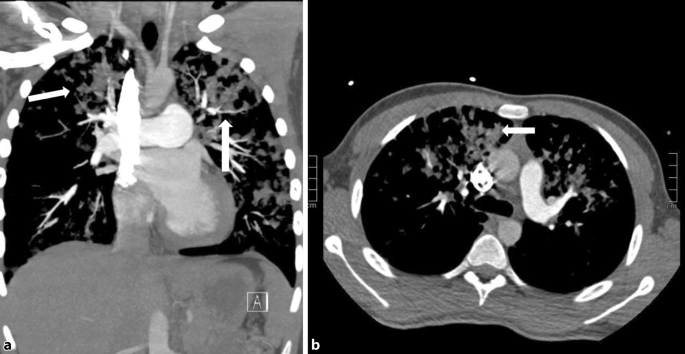

Dabei zeigten sich multiple perivaskuläre und interstitielle perihiläre, konfluierende Transparenzminderungen in Ober- und Mittellappenanteilen, ohne Zeichen der kardialen Dekompensation, am ehesten mit einem akuten Lungenödem vereinbar. Da die Echokardiographie eine pulmonale Hypertension moderaten Grades zeigte, entschied man sich für die Durchführung einer Thorax-Computertomographie zum Ausschluss einer Lungenembolie, und zwar mit der Einverständniserklärung der Eltern, auch wenn die akute Lungenembolie eine eher unwahrscheinliche Verdachtsdiagnose bei einem 15-Jährigen war (Abb. 2 und 3).

Abb. 2

figure 2

Lungenparenchym-Fenster axial mit bilateralen multiplen, vorwiegend perihilären, vaskulär-interstitiellen Konsolidierungen (oranger Pfeil)

Abb. 3

figure 3

Koronare (a) und axiale (b) Schichtführung mit unklaren vorwiegend perivaskulär angeordneten Konsolidierungen perihilär bds. (weiße Pfeile)

Die CT-Untersuchung zeigte dabei keine Füllungsdefekte in den Lungenarterien, sondern multiple, fleckige Parenchymkonsolidierungen mit perivaskulärer und interstitieller Disposition beidseits, unklarer Genese. Fünf Tage nach Therapiebeginn wurde ein erneutes Kontroll-Röntgen durchgeführt, das keine Konsolidierungen mehr zeigte (Abb. 4).